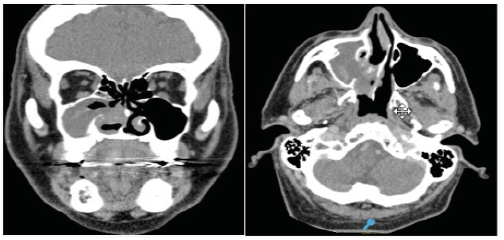

Male patient of 67 years of age. He consulted for intermittent epistaxis of the right nasal fossa of 3 months of evolution. He had a history of anticoagulant treatment. By nasal endoscopy, hematic remnants were observed, and the sinus computed tomography showed an occupation of the right maxillary sinus with bone destruction of the intersinusonasal wall (Figure 1). An endonasal approach was made with endoscopes and an ungiectomy, right maxillary antrostomy and resection of friable consistency polypoid tissue were performed. The deferred anatomopathological study reported: “Extensive areas with necrosis, hemorrhage and fibrin leukocytic exudate” compatible with an abscessed polyp associated with an organized hematoma. The patient was discharged 24 hours after the intervention and remained asymptomatic and without evidence of tumor in the endoscopic controls performed for 3 years.

Figure 1:CT Organized hematoma of the maxillary sinus with destruction of the intersinusonasal wall.